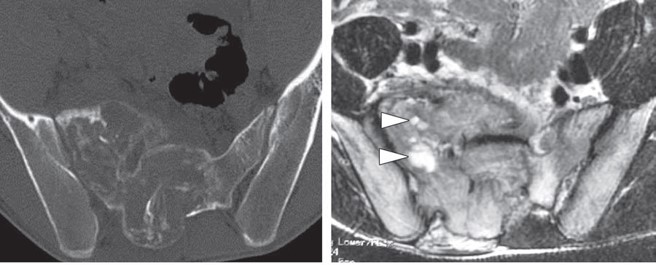

• CT

• T1WI

骨肉腫

• CT、T2WI

軟骨肉腫